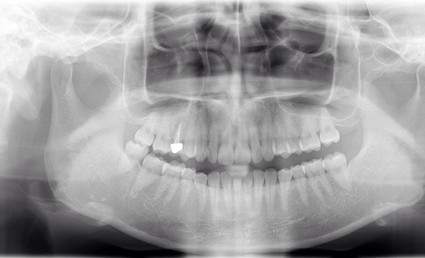

| 主訴 | 歯がしみる・見た目を改善したい |

| 状態 | 完全に神経が見えている状態だったので、根管治療を行ったのちセラミックで審美回復した症例。 |

| 料金 | 根管治療9万円+税、ファイバーコア2万円+税、仮歯1.5万円、E=MAXクラウン11.5万円+税(1本)×2本分=48万円 |

※根管治療と審美は別っていう医院が多いけど、包括的に治療できることが強み